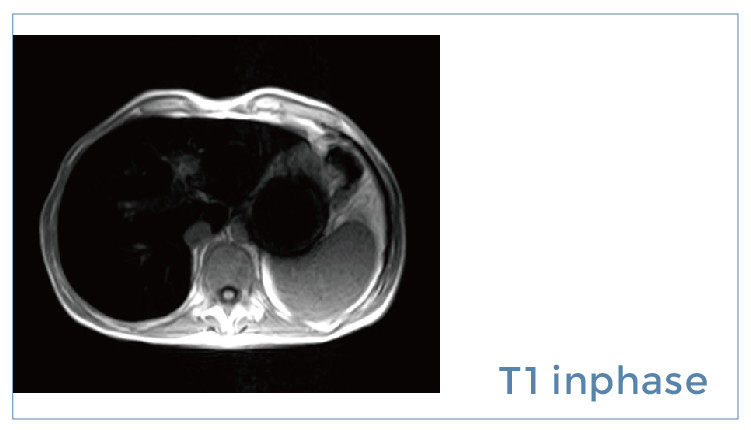

【朗润影像档案】20190914磁共振影像病例结果讨论